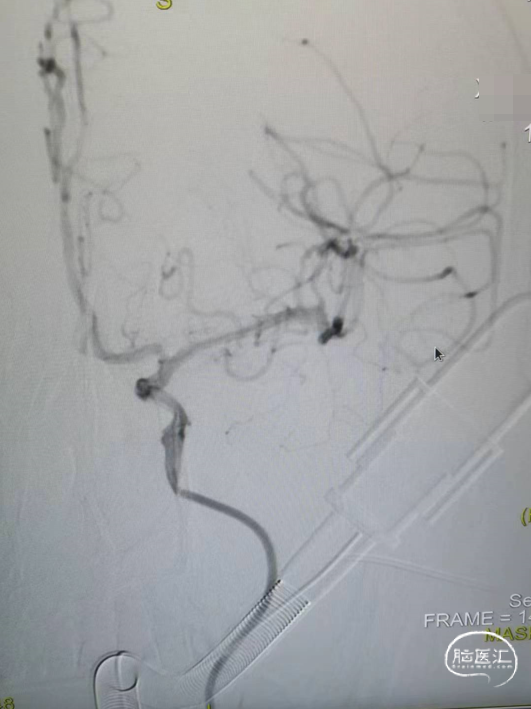

造影显示左侧的颈内动脉末端闭塞,中间导管造影显示大脑前和大脑中动脉显影,明确颈内末端闭塞。

中间导管到位之后送入RECO取栓支架 6*30cm、微导管,调整好微导管位置之后释放RECO取栓支架 6*30cm,支架展开之后血管血流通畅。

先负压抽吸,然后释放RECO取栓支架 6*30cm在负压下进行取栓操作。